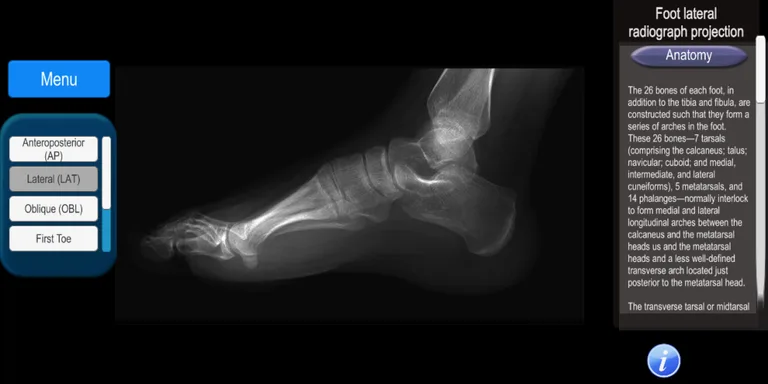

It is an app that allows the user to know the radiological projections that are used daily in a patient care. It covers all areas of the human body with more than 100 digital radiographs: skull, maxillofacial, spine, chest, abdomen, pelvis, upper and lower extremities.

The anatomy of the studied area is described, as well as the technique used for positioning the radiographic projection.